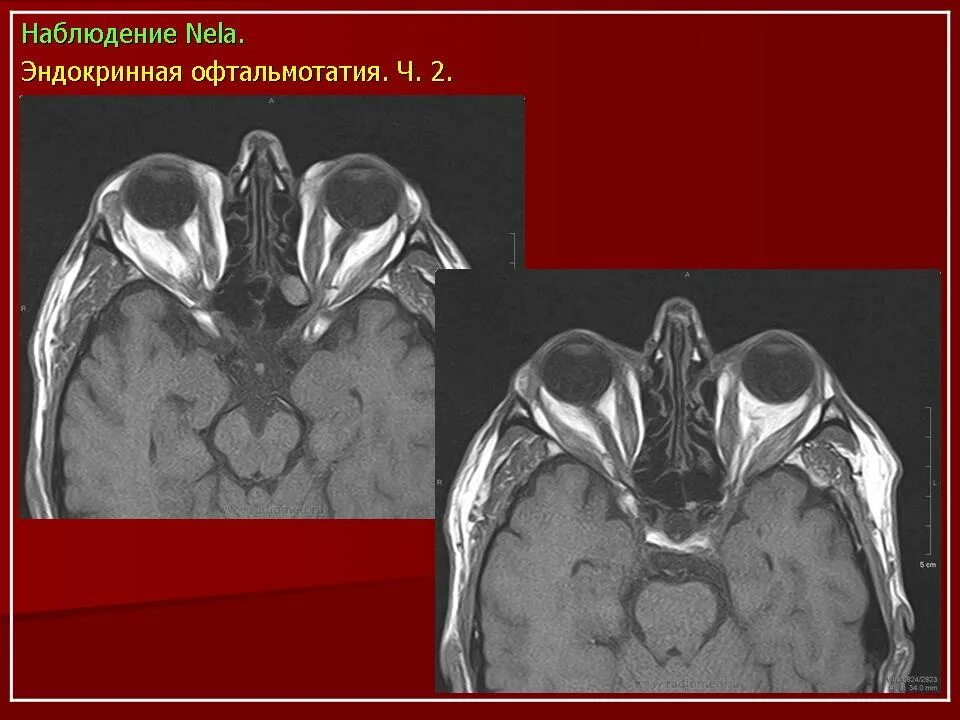

Данные кт